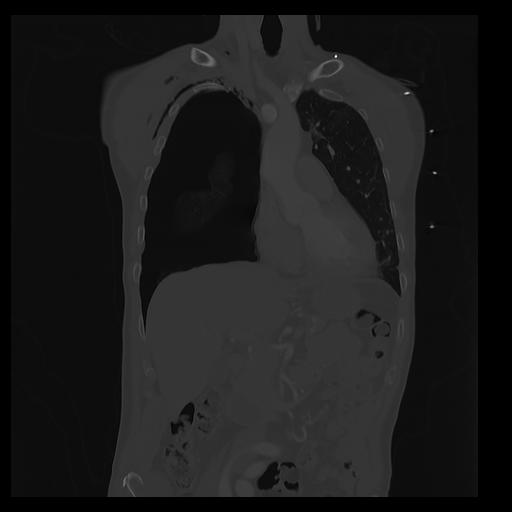

32 PULMON,CE,Coronal,3.000,PULMON,Coronal,